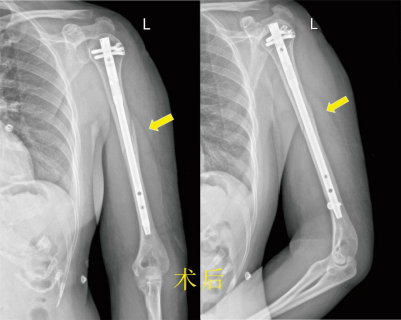

近期,家住经开区的周女士乘坐他人汽车时不幸发生车祸,左上臂撞伤,当时即感左上臂疼痛、畸形、不能活动。被120送入事故地附近医院,经X线检查提示:左肱骨中上段骨折,骨折端明显成角移位。在就诊医院,被告知需住院手术治疗。患者得知后自请转入市一医院经开区院区骨科住院治疗。

市一医院经开区院区骨科的医师接诊后详细询问病史、体格检查,明确的病情诊断,排除了胸腹等部位的内脏损伤。为了减轻患者的痛苦,帮助患者能够更快回到工作岗位,在通过CT的三维重建全面了解清楚骨折的情况后,决定给患者实行微创手术:闭合复位髓内针内固定术。 术前得到了患者和家属的积极配合,很快就将术前检查完善到位,排除手术禁忌症。经过麻醉、护理等的配合,顺利实行手术。术后给予镇痛、消肿等治疗后,1周后,患者左上臂肿胀几乎缓解了,只留下少许慢慢变淡了的瘀斑。术后12天患者拆线顺利出院。 在市一医院专家的帮扶下,市一医院经开区院区骨科以微创治疗为科室发展理念,开展了四肢骨折微创手术、脊柱的椎间孔镜手术、关节镜手术等治疗技术。不断攻克新的技术难关,提高医疗水平,提升患者就医体验,为患者提供更优质、安全、便捷医疗服务。 胡 斌 九江市第一人民医院骨三科主任 九江市第一人民医院经开区院区外二科主任 朱挺平